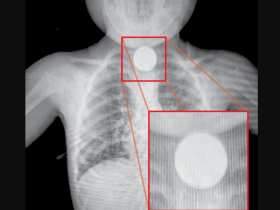

Em Ciudad del Este, menina de 2 anos que engoliu moeda está fora de perigo